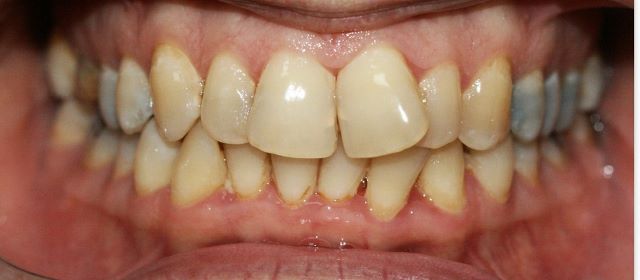

צפיפות שיניים

צפיפות מוגדרת כאשר ישנה חפיפה בין שיניים (האחת על גבי השנייה) ולרוב, רוחב קשת השיניים קטן מרוחב השיניים